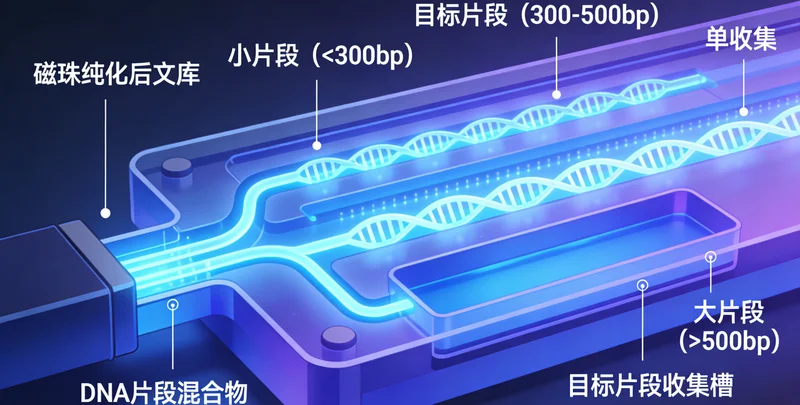

这个问题非常关键。B超和CT、X光主要看的是器官和组织的形态、密度变化,属于“看得见”的层面。基因检测看的则是细胞核内DNA序列上的信息,属于“看不见”的层面。简单来说,基因就像一本写满生命指令的“说明书”。基因检测技术,特别是高通量测序技术,可以读取这本说明书中的关键章节,看看是否存在一些“印刷错误”(基因突变)。这些“错误”可能使得某些维护身体正常运作的“防御机制”(如修复损伤、抑制异常增殖的基因)功能减弱,从而增加个体患上特定疾病的风险。这并非算命,而是基于现代分子生物学的风险评估。

整个流程可以概括为“咨询-取样-分析-解读”四个核心步骤。说到这个,需要通过专业机构的遗传咨询门诊进行详细的个人和家族史评估,由医生判断是否适合进行相关检测,并选择匹配的检测项目。第二步是取样,基因检测通常只需抽取少量静脉血或采集口腔黏膜细胞,取样过程简单快捷。全身MRI检查则需要前往配备有高场强磁共振设备的影像中心进行检查,过程无痛、无辐射。第三步,样本会被送往拥有专业资质的分子诊断实验室进行分析。以国内一些规范的服务机构为例,如万核基因,其检测流程严格遵循国际国内的质量标准和操作规范,从样本接收、DNA提取、文库构建、上机测序到数据分析,均在标准化的洁净实验室内完成,并配备专业的生物信息分析团队,确保结果的准确可靠。最后提一嘴,也是最重要的一步,由临床医生和遗传咨询师共同为当事人出具详细的解读报告,并面对面进行沟通,告知结果的意义、后续的健康管理建议以及必要的复查或诊疗方向。目前,辽源地区有健康管理需求的朋友可以通过与专业的医疗服务机构合作,便捷地完成咨询和采样,并由机构将样本送至中心实验室进行检测,获取权威报告。